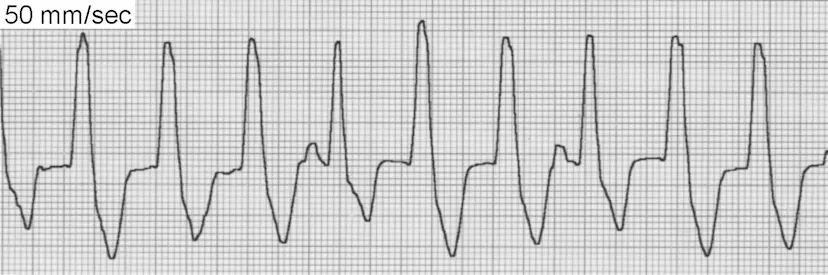

Figure 3 - ECG showing ventricular tachycardia with wide, bizarre QRS complexes

ECG Characteristics of VPCs/VT

- Wide QRS complexes (greater than 0.06 sec) with bizarre morphology

- No preceding P wave associated with the VPC

- T wave opposite in direction to the main QRS deflection

- Compensatory pause typically follows the VPC

- VPC morphology indicates origin: Upright (positive) VPCs in lead II suggest right ventricular origin; negative VPCs suggest left ventricular origin